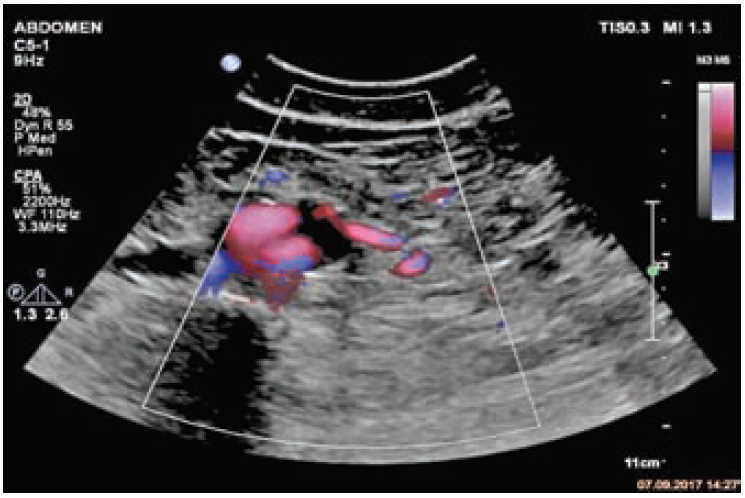

Рис. 1. Эндолик из нижней брыжеечной артерии.

По данным КТ сосудов брюшной полости с КУ: Состояние после эндопротезирования аневризмы инфраренального отдела аорты, подвздошных артерий. Эндолик II типа, вероятно из нижней брыжеечной артерии.

По данным ультразвукового исследования: Аневризматический мешок до 3,0 см. Визуализируется проходимый эндопротез. Ультразвуковые признаки эндолика II типа из нижней брыжеечной артерии (рис. 1, 2).

Рис. 2. Эндолик из нижней брыжеечной артерии.